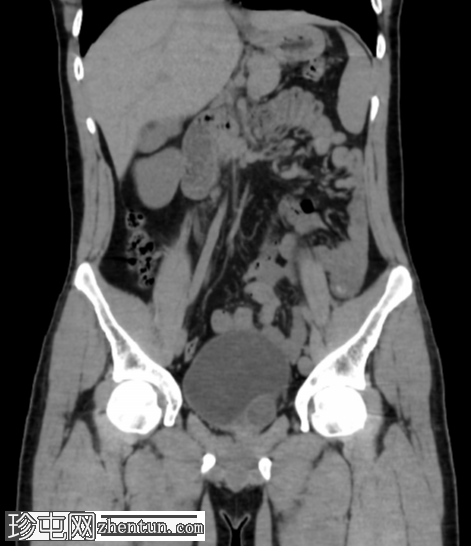

冠状位

平扫

左肾发育不全。

左侧精囊囊肿。

右肾代偿性肥大,右肾下盏可见微小结石。

齐纳综合征(Zinner syndrome)是由中肾管(沃尔夫管)异常三联征组成,包括单侧肾发育不全、同侧精囊囊肿和射精管梗阻。